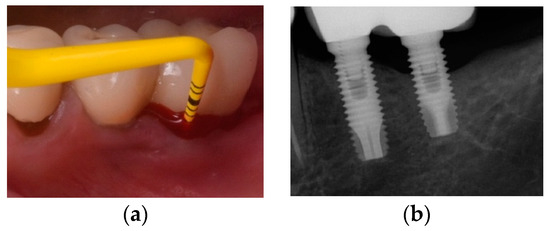

- Monje, A.; Blasi, G.; Nart, J.; Urban, I.A.; Nevins, M.; Wang, H.L. Soft Tissue Conditioning for the Surgical Therapy of Peri-implantitis: A Prospective 12-Month Study. Int. J. Periodont. Restor. Dent. 2020, 6, 899–906. [Google Scholar] [CrossRef] [PubMed]